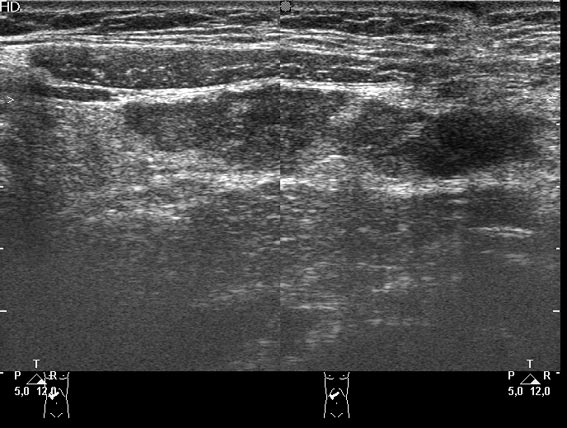

что-то в сальнике, но не инородное тело. может быть ошметок селезенки (аутотрансплантат)? васкуляризация есть?

у меня есть в архиве случай, когда мальчику 10 лет назад была выполнена спленэктомия (травма с разрывом, оперировали не у нас, и что там ему делали - непонятно). а я "нашла" селезенку, в типичном месте, S ее составляла 9 см2.

Если в типичном месте и не выполнялась аутотрансплантация, то это может быть гипертрофия т.н. дополнительной селезенки.